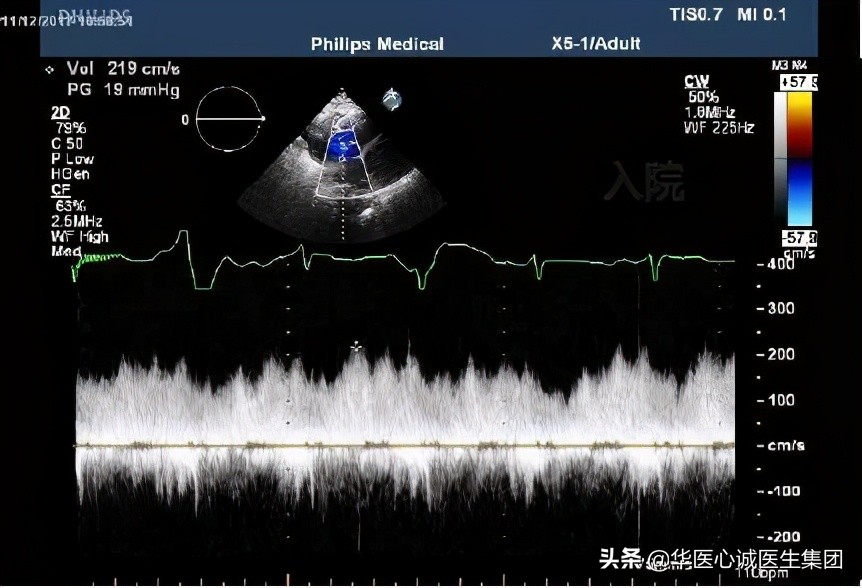

左图:入院时测量的房缺分流速度和压差(19mmHg),右房压至少15mmHg ➜ 导致左房压很高,预计40mmHg ➜ 充分提示左室充盈压非常高。

右图:治疗1周后,血压下降,左房与右房的压差降至4mmHg,接近正常水平。因为左房压下降,左心衰得到控制,患者症状立即好转。